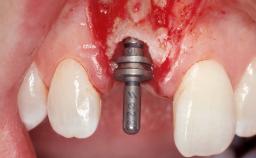

Immediate Flapless Placement of an Implant in a Maxillary Right Lateral Incisor Site

This 43-year-old male patient, a non-smoker, came to our practice because of a fracture of tooth 12 caused by a bicycle accident. Due to the combined para- and infrabony crown and root fracture, tooth extraction, and subsequent implant placement were suggested to the patient as the therapy of choice. The patient had high esthetic expectations with regard to the treatment outcome and asked for an immediate fixed provisional restoration. His individual esthetic risk profile summed up to a medium esthetic risk.

Placement Protocol Immediate implant placement

Tooth Site Maxillary incisor or canine

Socket Morphology Single-root socket

Socket Integrity Sufficient, with intact bone walls

Loading Protocol Immediate